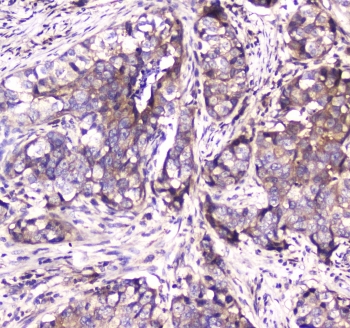

IHC testing of FFPE human breast cancer tissue with SDHB antibody at 1ug/ml. Required HIER: steam section in pH6 citrate buffer for 20 min and allow to cool prior to staining.